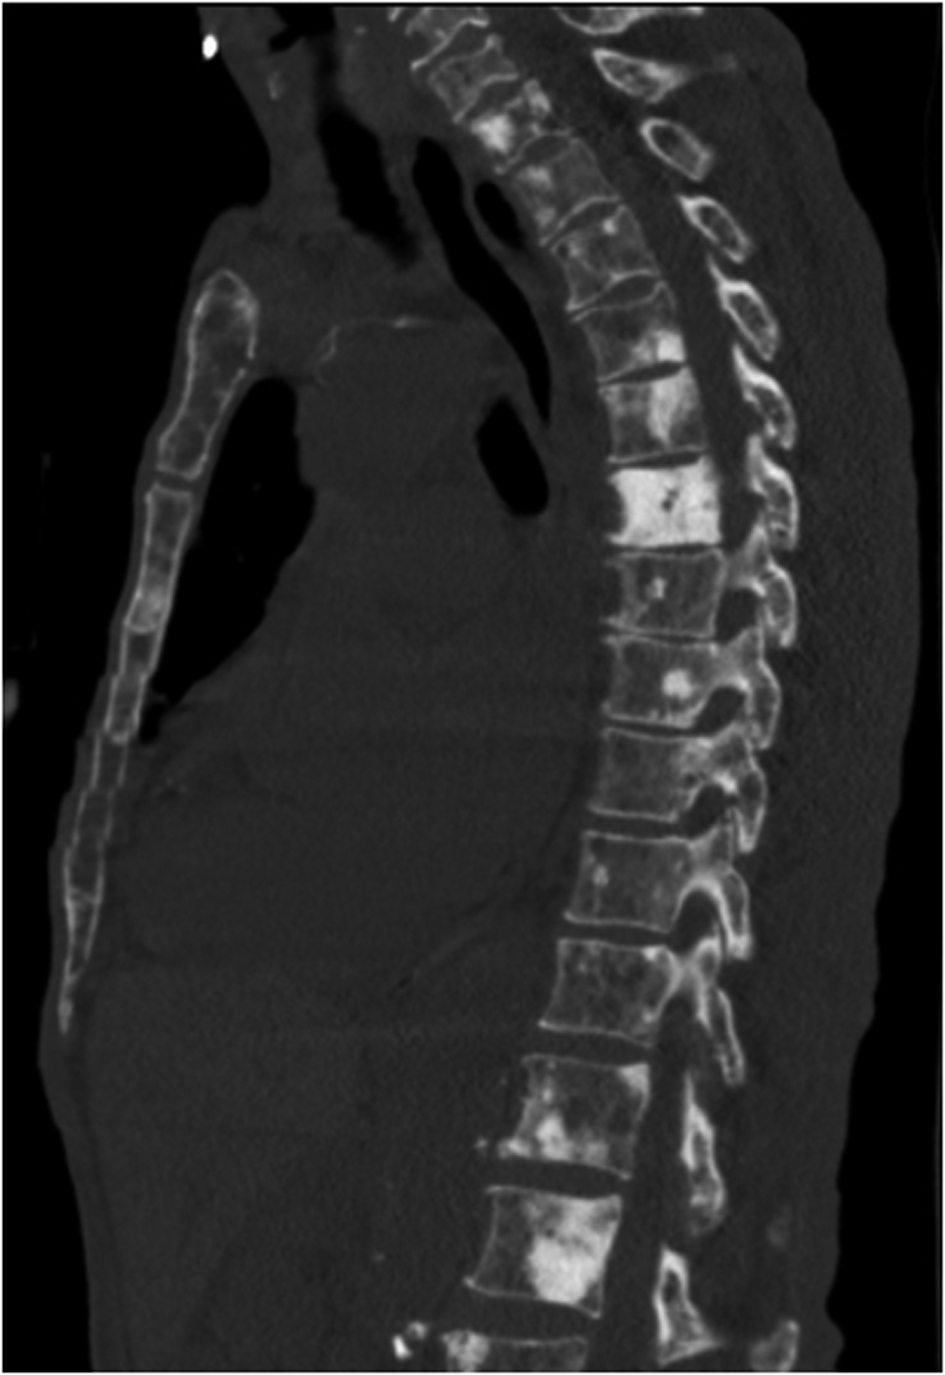

Serum electrophoresis revealed M spike with elevated IgG monoclonal protein with kappa light specificity. Urine also showed bence-jonce proteinuria with free kappa light chain. Beta 2 microglobulin levels were 32.5 mg/L. Cosyntropin stimulation test revealed primary adrenal insufficiency. Patient was started on IV hydration, dexamethasone and fludrocortisone. Patient’s electrolyte normalized on treatment and renal failure improved. Bone survey revealed lytic and blastic lesions in the vertebrae and other bones (Fig. 3). CT scan of chest also revealed large left 9th rib lesion with extra pleural mass effect. CT chest reconstruction revealed same blastic lesions in thoracolumbar vertebrae (Fig. 4). PSA, CEA and CA 19 - 9 levels were within normal limits and pelvic sonogram did not reveal any prostate nodule. HIV testing was negative and hepatitis testing revealed past infection with hepatitis B. Lymph node biopsy revealed reactive follicular hyperplasia with dermatopathic changes (Fig. 5). No other focus of malignancy was noted on CT chest, abdomen, pelvis and head. Before bone biopsy, patient’s condition deteriorated rapidly and developed DIC, GI bleed and retroperitoneal hematoma which lead to demise of the patient. Based on available data diagnosis of multiple myeloma with IgG kappa chain specificity was made.

![]() Click for large image | Figure 4. Reconstruction images of the CT chest showing multiple osteoblastic lesions in thoraco-lumbar vertebrae. |